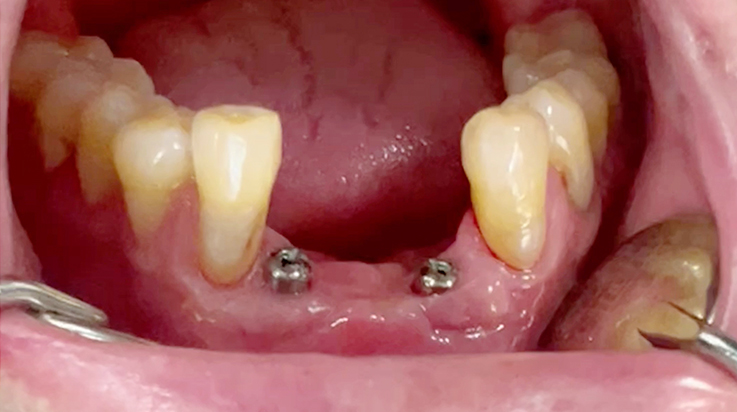

A surgical procedure using non resorbable membrane

• A surgical procedure using non resorbable membrane 7